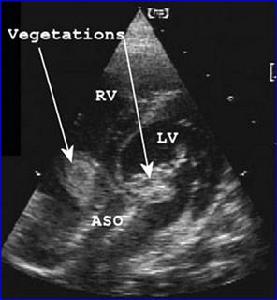

亞急性感染性心內膜炎感染性心內膜炎有一定的好發部位,多發生於血流衝擊或局部產生渦流的部位,如二尖瓣關閉不全的心房面,主動脈瓣關閉不全的心室面,室間隔缺損的右心室面動脈導管未閉的肺動脈內膜面等。

亞急性感染性心內膜炎贅生物所附著的瓣膜有炎性反應及灶性壞死,其周邊有淋巴細胞,纖維細胞及巨細胞浸潤。壞死細胞周圍有新生毛細血管,結締組織及肉芽組織,當炎症消退,贅生物纖維化,表面為內皮細胞所覆蓋,經治療痊癒的病例,三個月才能完全癒合,未治癒的病例,癒合與炎症反應交叉存在。贅生物大而易碎,脫落可致臟器及周圍動脈栓塞,如腎、腦、脾、腸系膜及四肢等,先心病並感染性心內膜炎病例,多並發肺栓塞,局部細菌滋長可使瓣葉產生潰瘍或穿孔,腱索及乳頭肌斷裂及細菌性動脈瘤。抗原-抗體複合物在腎血管球沉積,可發生腎血管球性腎炎,由於免疫反應引起小動脈內膜增生,阻塞及小血管周圍炎,表現為皮膚及黏膜的淤點,發生於手指、足趾末端的掌面,稍高於皮面,有壓痛,5-15mm大小,稱奧氏(Osler)結節,後掌及足趾有數毫米大小的紫紅色斑點,稱為Janeway氏結節。

5、超聲心動圖心瓣膜或心內膜壁有贅生物,及固有心臟病的異常表現。